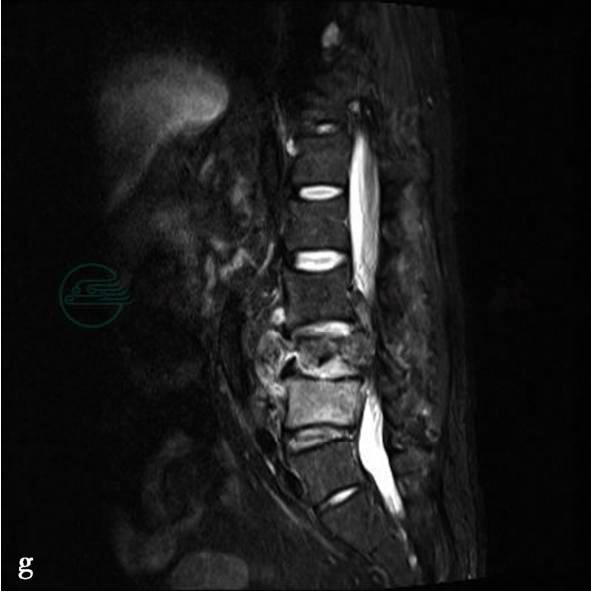

(2)病例5-2-8:

CT平扫及MRI平扫、增强扫描。

图2 d、f、g,CT平扫示矢状面重建图像显示腰椎生理曲度略变直。L2、L3椎体内可见多发斑片状溶骨性骨质破坏,边缘清楚,周围无骨质硬化。L2/3椎间隙变窄,骨性椎管无变窄,椎旁软组织稍肿胀。图2a、b、c,MRI示腰椎生理曲度略变直。L2/3椎间隙变窄。L2、L3椎体相对缘骨性终板骨质破坏。图2b,T1WI呈低信号。图2a,T2WI呈稍高信号,信号不均匀图2c,STIR序列呈高信号。L2、L3椎体在T1WI(图b)上呈均匀低信号,在STIR(图d)上呈均匀高信号。椎旁软组织肿胀,多发小囊状信号影。硬膜囊略受压

(2)病例2,(腰2、3椎体)结核(边缘型)。